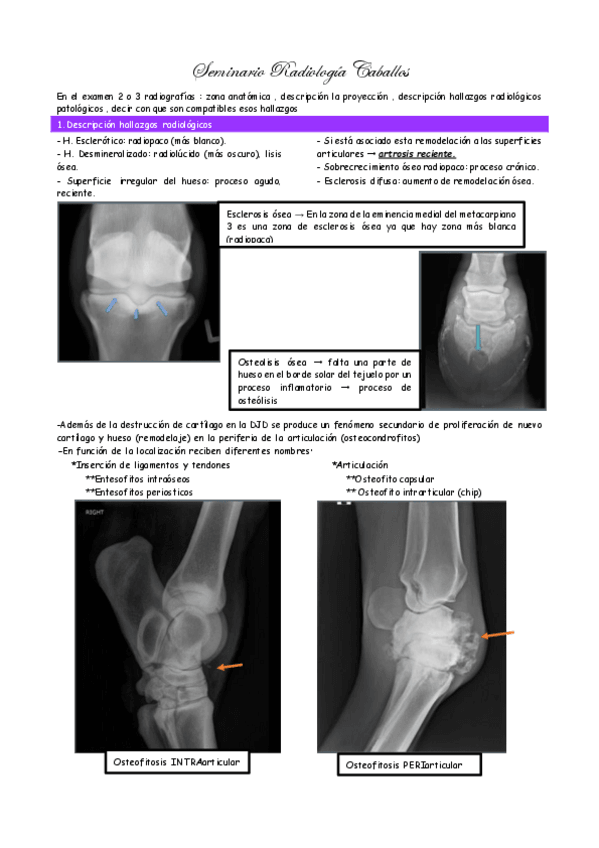

Seminario-PAEE-Radiologia-Equidos.pdf